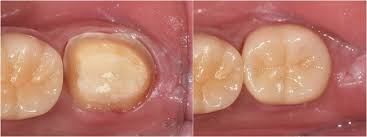

- 재접착 가능 시 임시/영구 접착 → 안 되면 새 크라운 제작

- 임시 크라운 장착 후 최종 크라운 장착 (1~2주 소요)